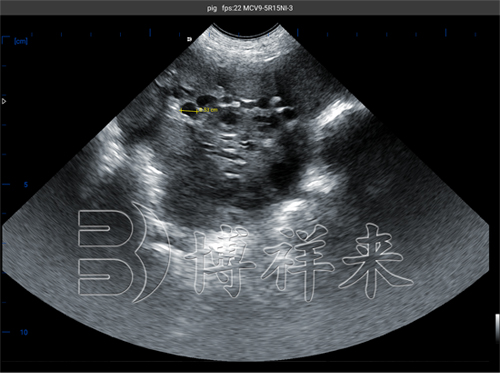

猪用B超机测母猪卵泡大小B超图像

在B超图像中,卵泡表现为:

圆形或椭圆形的黑色无回声区;

边缘清晰、轮廓光滑;

周围有一圈稍强回声的卵巢组织包绕。

这是因为卵泡内部充满液体,声波穿透后被吸收或折射,形成典型的黑色影像。

在发情周期的不同阶段,卵泡的大小、数量及排列分布都会发生变化,这为B超判读提供了重要依据。

| 排卵前期 | 6–8 mm | 单个或少数卵泡明显突出,壁较薄 | **配种时机,排卵即将发生 |